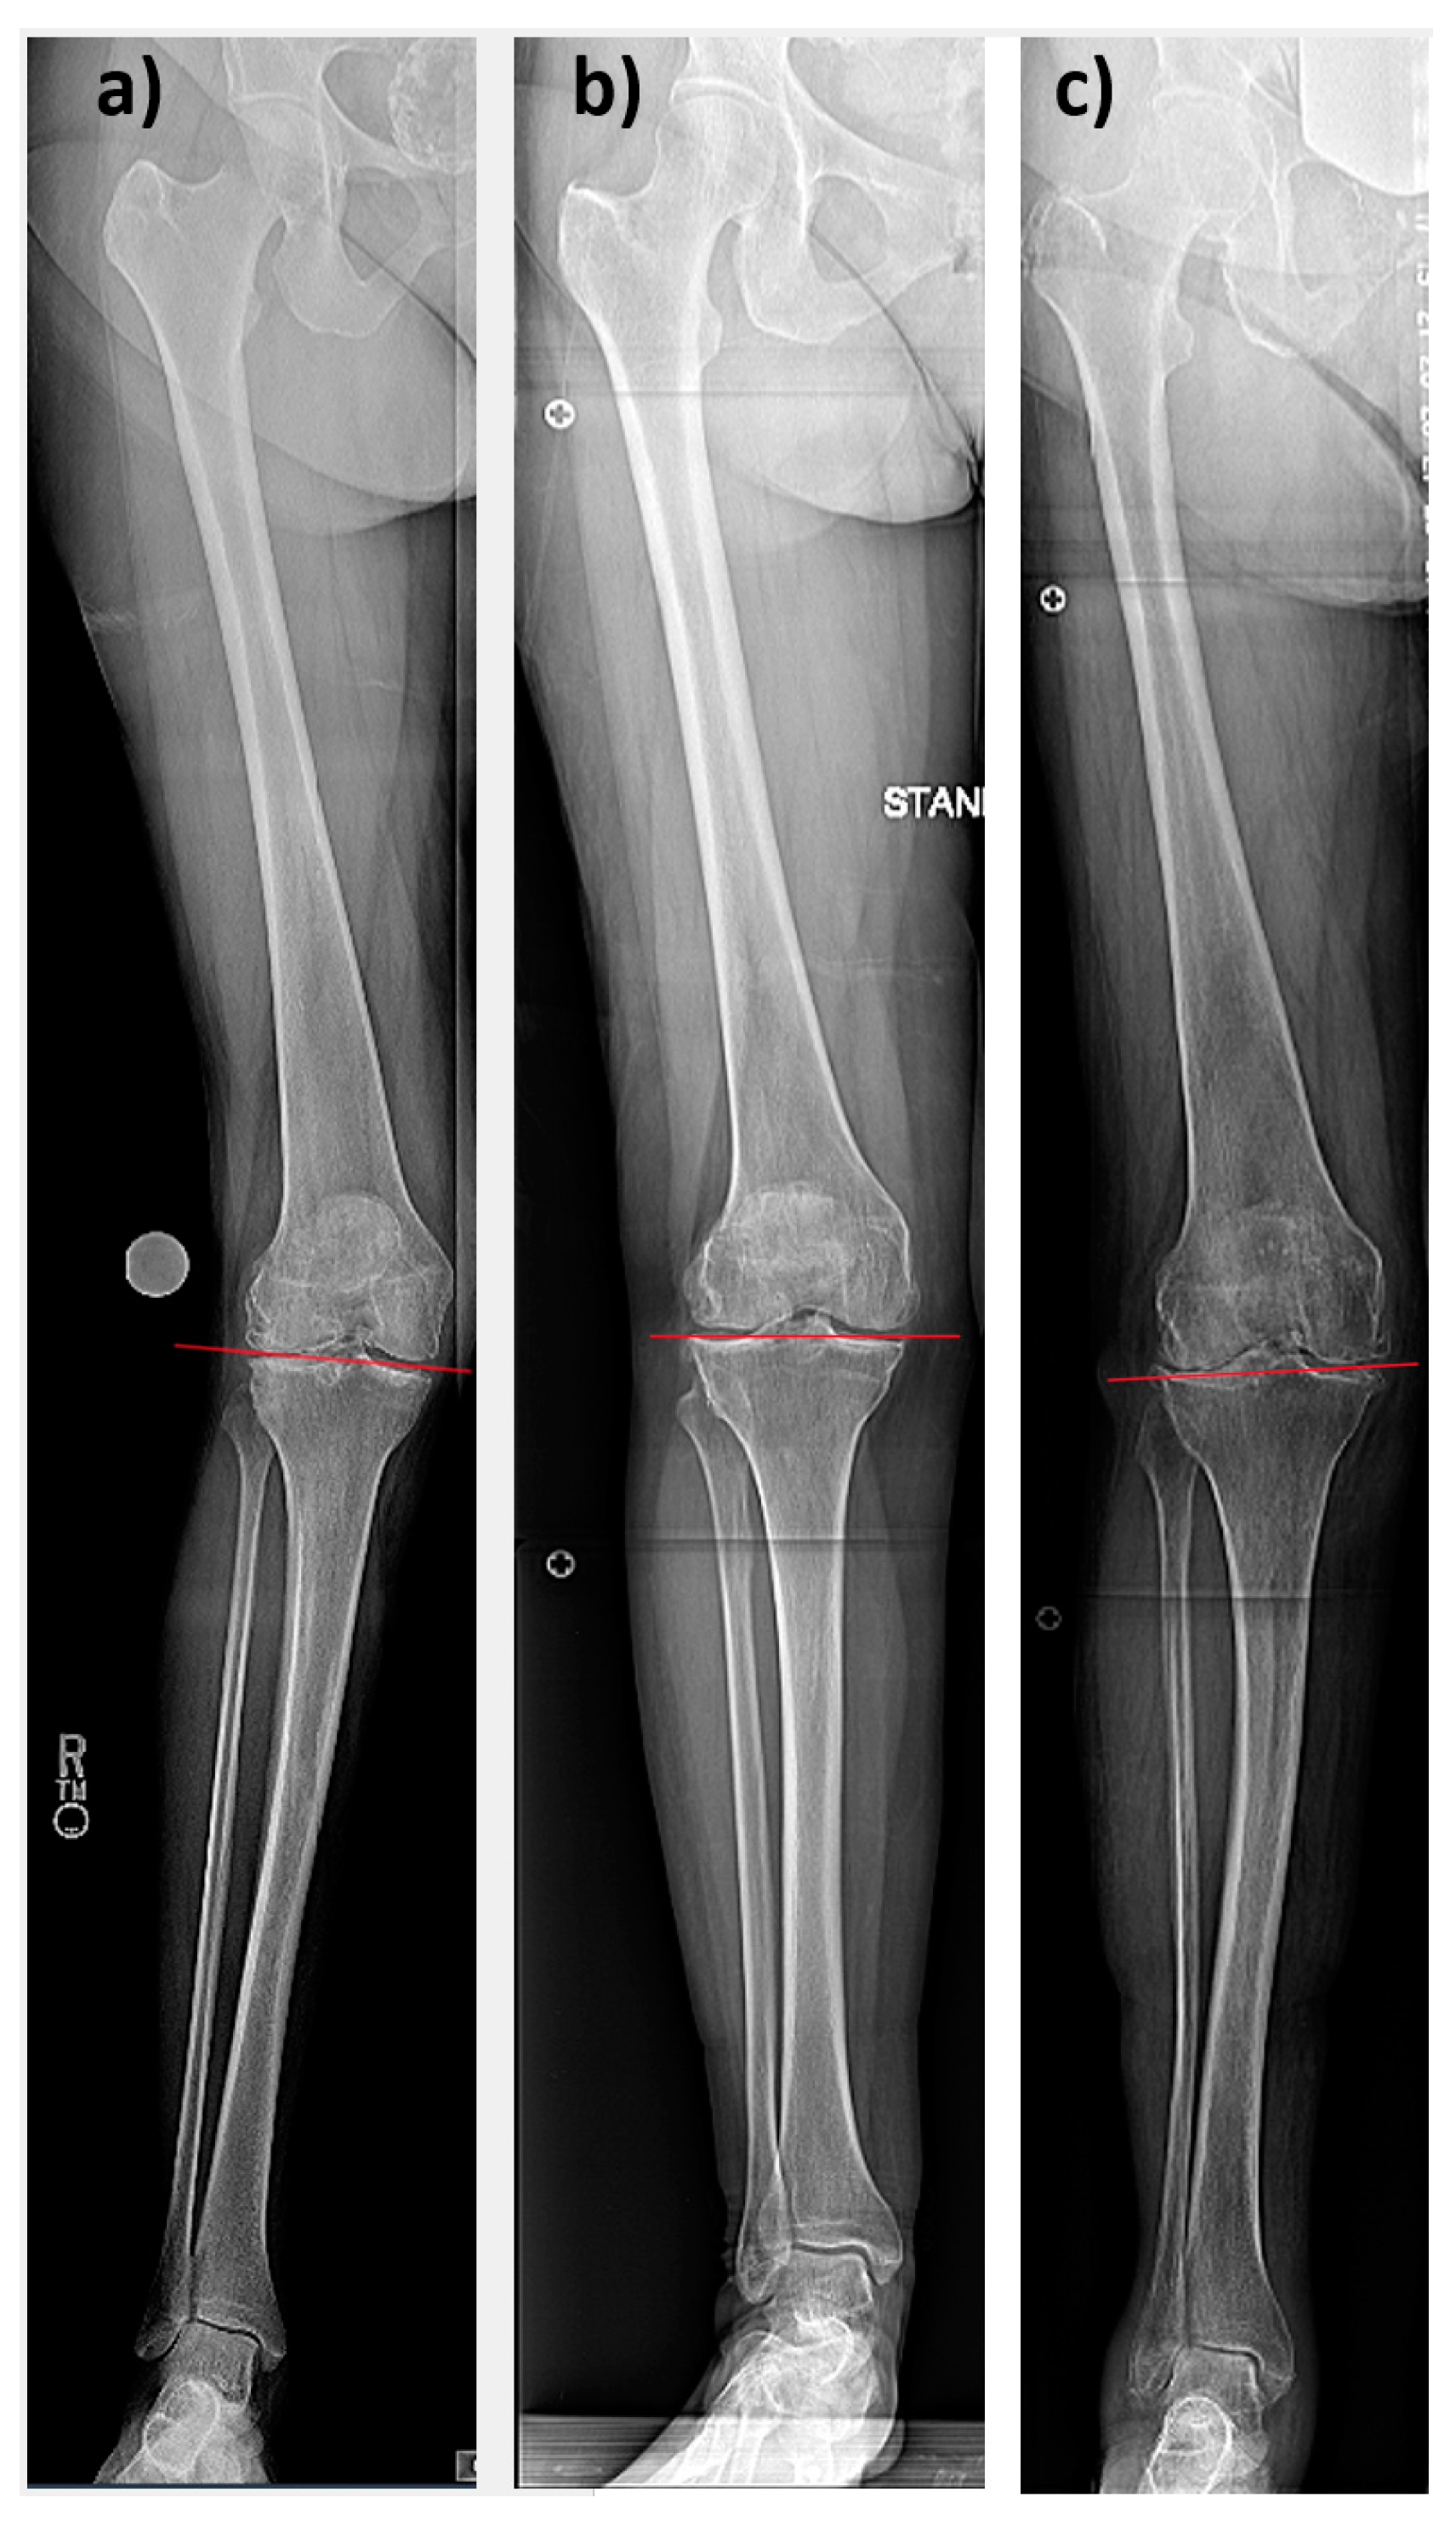

3.1. Preoperative Alignment

3.2. Postoperative Alignment and Alignment Chances